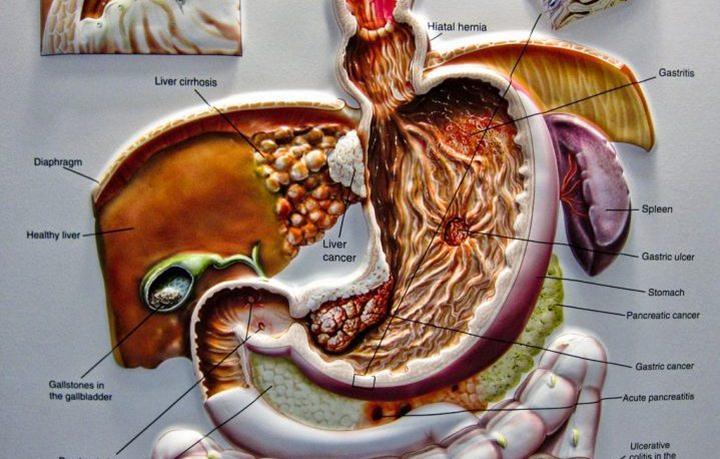

Dealing with cancer is difficult, but when the verdict is pancreatic cancer, the survival rate is only 25 percent for the first five years after the diagnosis. Like all other cancers, staging occurs from the beginning. The oncologist will base the stages upon various factors, such as if the...

The pancreas is a six-inch-long organ located behind the lower part of your stomach. Its function is to secrete the hormones and glucagon that help regulate sugar metabolism and enzymes that aid digestion. When the hormones are not working properly, diabetes is often the result. Pancreatic cancer occurs when...

The pancreas is the organ that is responsible for delivering enzymes to the body that are essential for digesting food and metabolizing sugar. Cancer of the pancreas occurs when the tissues of the organ are overtaken by harmful tumors that inhibit the way the pancreas functions. Even when pancreatic...